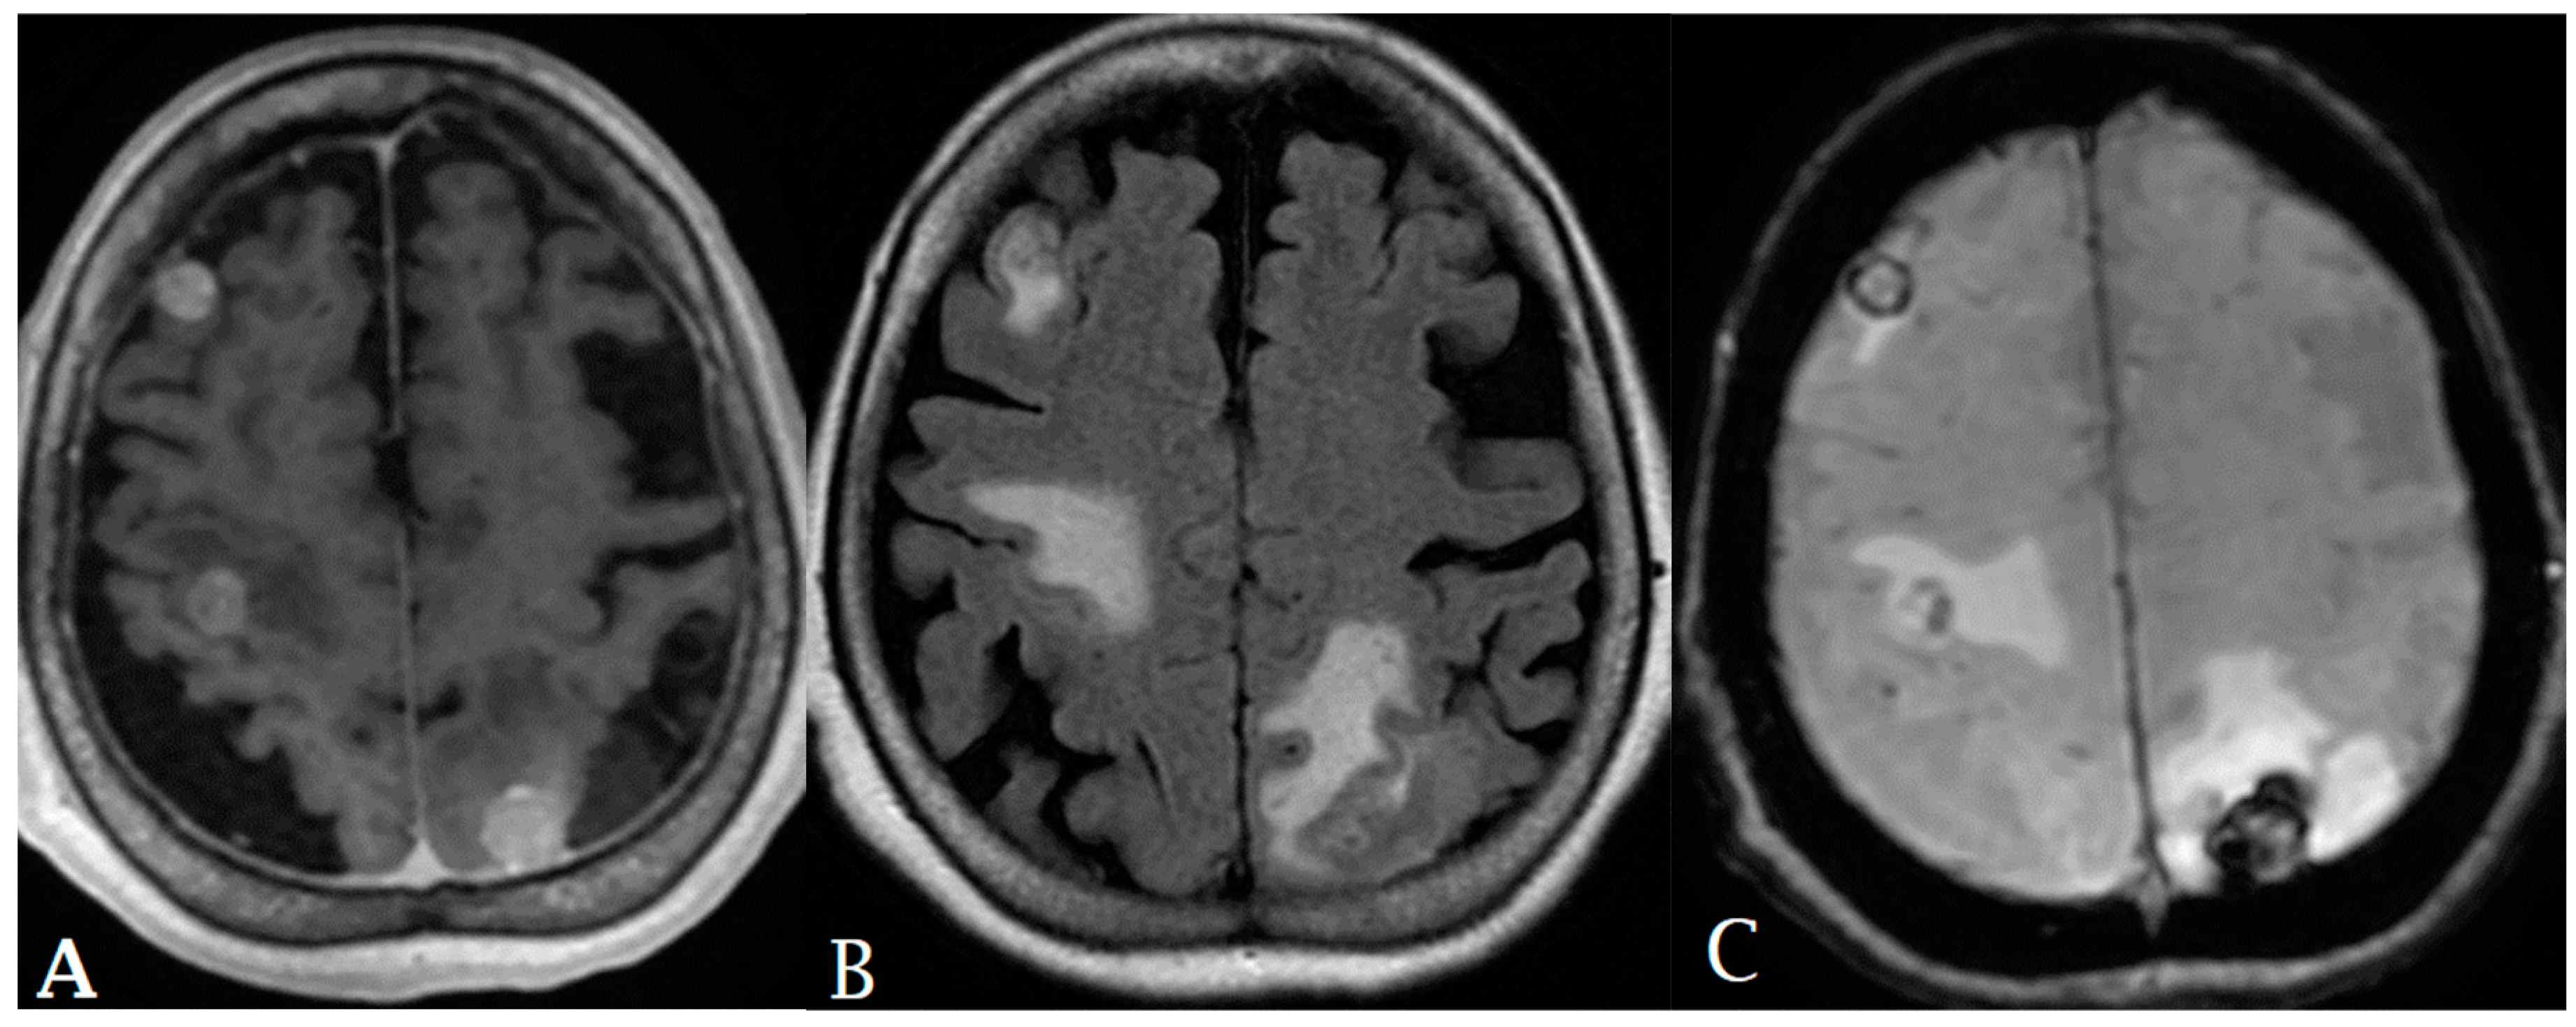

- Elshafeey, N.; Kotrotsou, A.; Hassan, A.; Elshafei, N.; Hassan, I.; Ahmed, S.; Abrol, S.; Agarwal, A.; El Salek, K.; Bergamaschi, S.; et al. Multicenter study demonstrates radiomic features derived from magnetic resonance perfusion images identify pseudoprogression in glioblastoma. Nat. Commun. 2019, 10, 3170. [Google Scholar] [CrossRef] [PubMed]

- Park, J.E.; Kim, H.S.; Goh, M.J.; Kim, S.J.; Kim, J.H. Pseudoprogression in Patients with Glioblastoma: Assessment by Using Volume-weighted Voxel-based Multiparametric Clustering of MR Imaging Data in an Independent Test Set. Radiology 2015, 275, 792–802. [Google Scholar] [CrossRef] [PubMed]

- Kim, J.Y.; Park, J.E.; Jo, Y.; Shim, W.H.; Nam, S.J.; Kim, J.H.; Yoo, R.-E.; Choi, S.H.; Kim, H.S. Incorporating diffusion- and perfusion-weighted MRI into a radiomics model improves diagnostic performance for pseudoprogression in glioblastoma patients. Neuro-Oncol. 2018, 21, 404–414. [Google Scholar] [CrossRef] [PubMed]